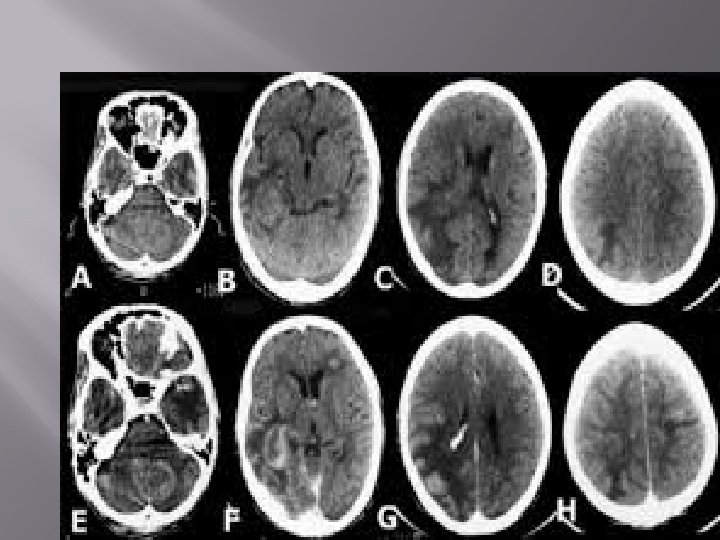

� A computerized tomography (CT) scan combines a series of X-ray images taken from different angles around your body and uses computer processing to create cross-sectional images (slices) of the bones, blood vessels and soft tissues inside your body. CT scan images provide more-detailed information than plain Xrays do.

� A CT scan has many uses, but it's particularly well-suited to quickly examine people who may have internal injuries from car accidents or other types of trauma. A CT scan be used to visualize nearly all parts of the body and is used to diagnose disease or injury as well as to plan medical, surgical or radiation treatment.